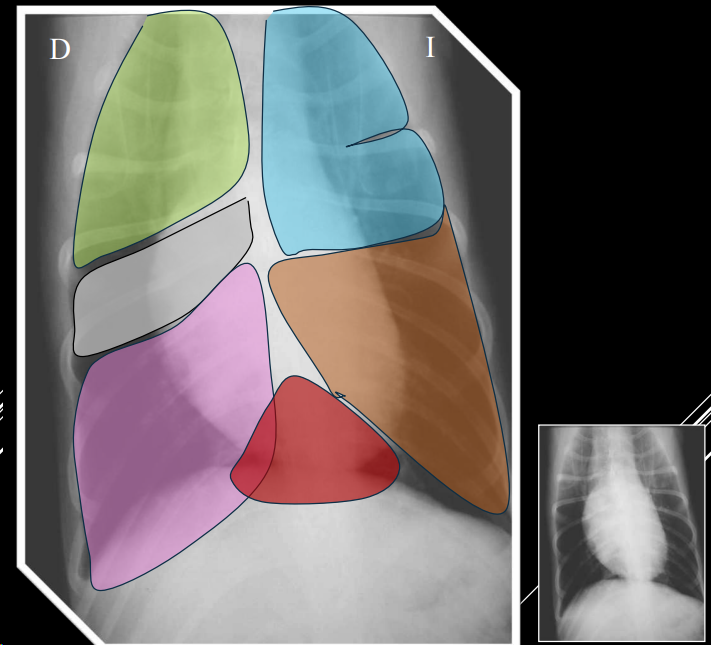

Proyección DV:

- 11–1: arco aórtico.

- 1–2: arteria pulmonar.

- 2–3: orejuela AI.

- 3–5: ventrículo izdo.

- 5–9: ventrículo dcho.

- 9–11: aurícula dcha.

Proyección LL:

- Craneodorsal: aorta y atrio derecho.

- Craneoventral: ventrículo derecho.

- Caudodorsal: atrio izquierdo.

- Caudoventral: ventrículo izquierdo.